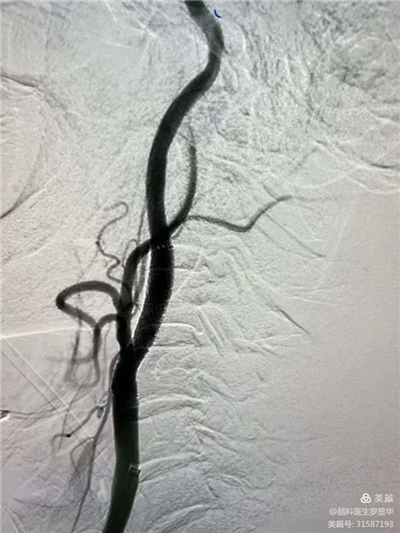

手術(shù)過程:球囊擴(kuò)張后,protege支架到位

術(shù)后造影示狹窄解除